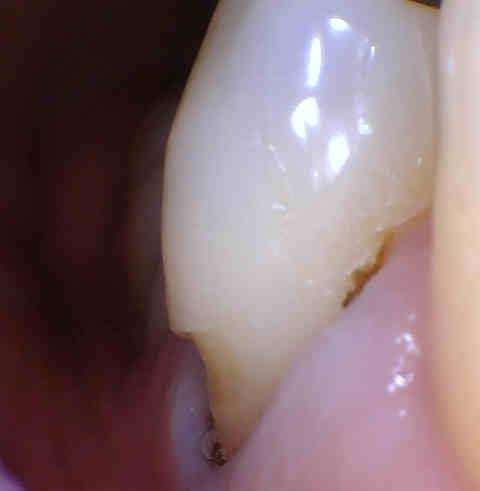

This patient complained of sensitivity to sweets and cold drinks along her gums. Turns out that a significant amount of enamel had broken down along the gum line. Combined with gum recession, her tooth's root surface was exposed, causing the sensitivity. Our Los Gatos dentist bonded a tooth-colored filling on her tooth and polished it in order to blend with the natural tooth. Not only did this bonding protect the tooth from sensitivity, so she could enjoy her favorite foods again, but it also improved the cosmetic appearance!